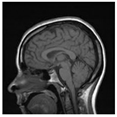

| Original Image | Marked Image | Encrypted Image (Chaotic) | Decrypted Image | Correlation between Extracted Blocks and Original Blocks |

![]() | ![]() PSNR = 35.99 dB SSIM = 0.97 | ![]() PSNR = 12.17 dB SSIM = 0.1035 | ![]() PSNR = 35.99 dB SSIM = 0.97 | ![]() |